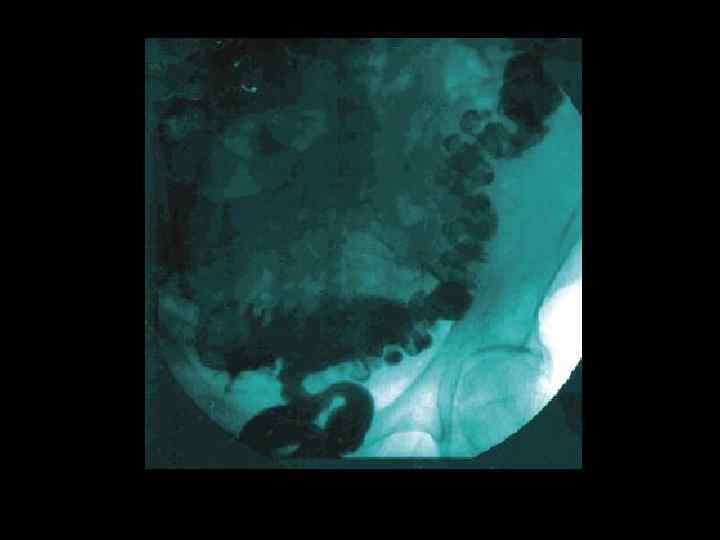

УЗИ желчного пузыря при остром холецистите. Выявляется растянутый желчный пузырь (толстая стрелка) с камнем, вколоченным в устье пузырного протока (тонкая стрелка), отбрасывающим акустическую тень. Стенка желчного пузыря значительно утолщена.

Ультразвуковыми признаками острого холецистита являются • • • утолщение стенок желчного пузыря более 4 мм "двойной контур" стенки увеличение размеров желчного пузыря перивезикальной жидкости положительный УЗ-признак Мерфи (локальное напряжение желчного пузыря под УЗ-датчиком). • По данным УЗИ можно судить о форме воспаления желчного пузыря